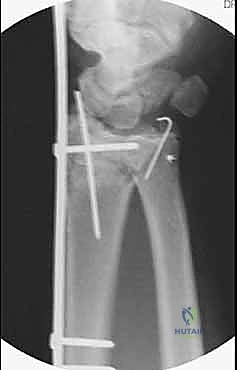

| الصفيحة الجسرية (Bridge Plating) | صفيحة طويلة تمتد من الساعد وتعبر المفصل لتثبت في عظام اليد. | الكسور شديدة التفتت، فقدان العظم، والإصابات المتعددة. | يتطلب جراحة ثانية لإزالة الصفيحة بعد التئام العظم (بعد 3-4 أشهر). |

تعتمد هذه التقنية المتقدمة على مبدأ إبقاء المفصل مشدوداً ومثبتاً من الخارج. الصفيحة تعمل كـ "جسر" يعبر فوق منطقة الدمار الشامل في العظم، وترتكز على عظم سليم في الساعد وعظم سليم في اليد. هذا الجسر يمنع العظم المفتت من الانهيار ويسمح للشظايا الصغيرة بالالتئام في مكانها الصحيح بفضل الشد الطبيعي للأربطة المحيطة.

5. وضع البراغي النهائية (Screw Insertion)

يتم تثبيت الصفيحة بقوة باستخدام براغي متطورة (Locking Screws) في عظم الساعد السليم وعظم المشط في اليد. هذه البراغي تلتحم بالصفيحة لتشكل هيكلاً صلباً للغاية لا يتأثر بالحركة.

6. التحقق الإشعاعي (Fluoroscopic Verification)

أثناء العملية، يستخدم الدكتور هطيف جهاز الأشعة المباشر للتأكد من المحاذاة المثالية للعظم واستعادة الطول والزوايا التشريحية الصحيحة للرسغ.

- بعد 3 إلى 4 أشهر: يكون العظم المفتت قد التأم بالكامل وأصبح كتلة صلبة. في هذه المرحلة، يتم إجراء جراحة صغرى بسيطة جداً (Day Case Surgery) لإزالة الصفيحة الجسرية.

لا، هذا هو الاختلاف الرئيسي عن الصفائح العادية. الصفيحة الجسرية تعبر المفصل وتمنع حركته، لذا يجب إزالتها بمجرد التئام العظم (عادة بعد 12 إلى 16 أسبوعاً) للسماح للرسغ بالحركة الطبيعية.